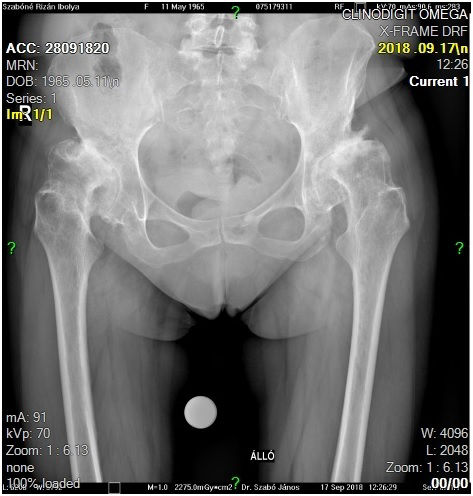

29 éves pályám során közel ezer térdprotézist és több mint kétezer csípőprotézist ültettem be. Az utóbbi években egyre több, nagy műszer igényű, összetett protézis revíziós műtétet végzek.

Fő érdeklődési köröm a biomechanika, műszerfejlesztés, új műtéti technikák kidolgozása és a nagyízületi endoprotetika.